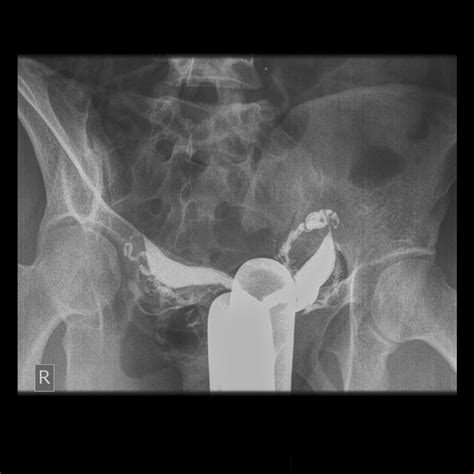

When individuals search for Didelphic Uterus Pictures, they are often seeking clarity on how their anatomy differs from the standard uterine structure. Medical imagery, such as MRIs, ultrasounds, and 3D pelvic reconstructions, provides the best visual representation of this double structure. Unlike a bicornuate uterus—where the two horns are connected—the Didelphic uterus consists of two completely independent units.

Viewing these medical images helps patients understand why they may experience certain symptoms. For example, the presence of two cervices is a hallmark feature visible in clinical scans. Understanding these visuals can help patients communicate more effectively with their gynecologists during consultations.

| Hysterosalpingography | Used to observe the shape of the uterine cavities using dye. |